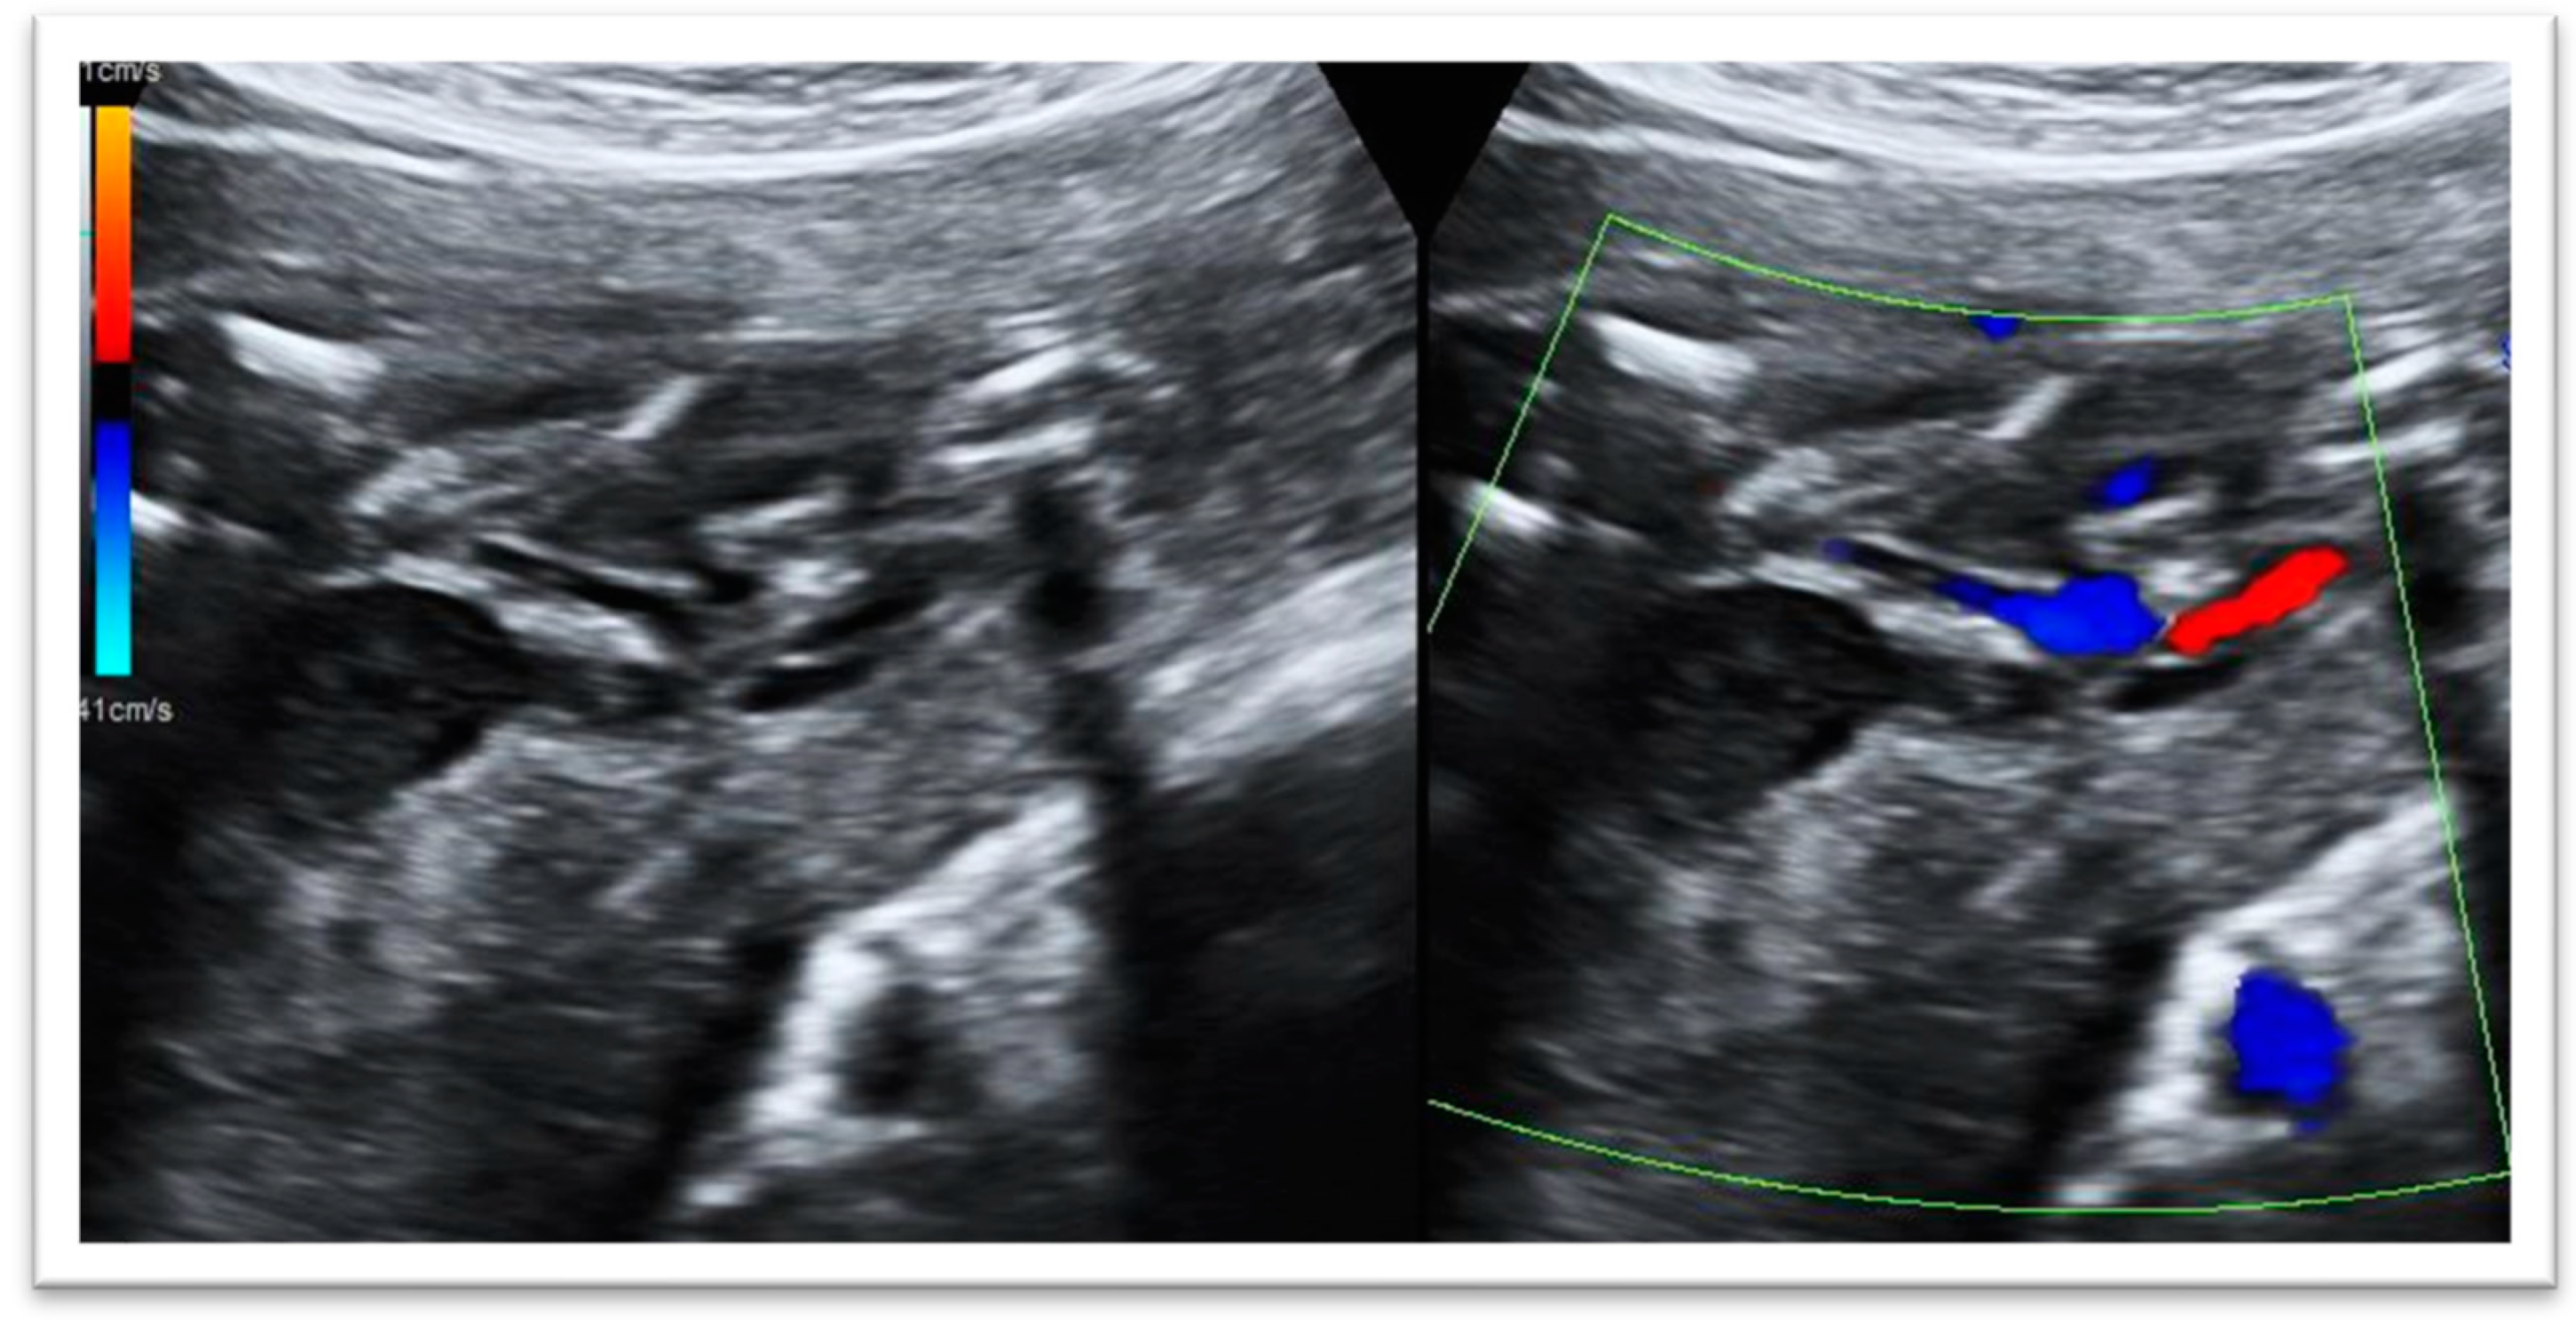

The ultrasound scan in our fetal medicine department, performed at 23 weeks, demonstrated the following abnormalities in the fetus (Figure 1):

• Fetal megacystis: increased bladder wall thickness, bladder dilatation and the presence of the ‘keyhole sign’.

Figure 1. Assessment of the fetal bladder: the keyhole sign is an ultrasonographic marker which refers to the appearance of the dilatation of the proximal urethra and a thick-walled distended bladder and single umbilical artery.